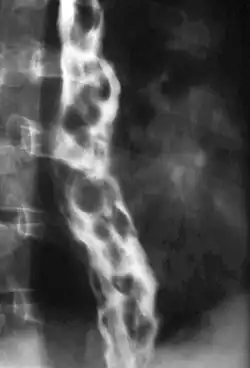

The upper two thirds of the esophagus are drained via the esophageal veins, which carry deoxygenated blood from the esophagus to the azygos vein, which in turn drains directly into the superior vena cava. These veins have no part in the development of esophageal varices. The lower one third of the esophagus is drained into the superficial veins lining the esophageal mucosa, which drain into the left gastric vein, which in turn drains directly into the portal vein. These superficial veins (normally only approximately 1 mm in diameter) become distended up to 1–2 cm in diameter in association with portal hypertension.

Normal portal pressure is approximately 9 mmHg compared to an inferior vena cava pressure of 2–6 mmHg. This creates a normal pressure gradient of 3–7 mmHg. If the portal pressure rises above 12 mmHg, this gradient rises to 7–10 mmHg.[5] A gradient greater than 5 mmHg is considered portal hypertension. At gradients greater than 10 mmHg, blood flowing through the hepatic portal system is redirected from the liver into areas with lower venous pressures. This means that collateral circulation develops in the lower esophagus, abdominal wall, stomach, and rectum. The small blood vessels in these areas become distended, becoming more thin-walled, and appear as varicosities.

Dilated submucosal veins are the most prominent histologic feature of esophageal varices. The expansion of the submucosa leads to elevation of the mucosa above the surrounding tissue, which is apparent during endoscopy and is a key diagnostic feature. Evidence of recent variceal hemorrhage includes necrosis and ulceration of the mucosa. Evidence of past variceal hemorrhage includes inflammation and venous thrombosis.